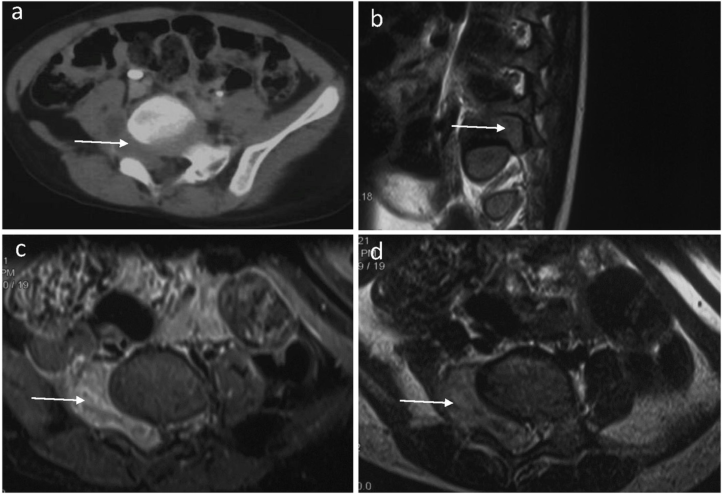

盆腔增强CT扫描显示右侧L5、S1椎间孔处有一密度不均的肿块 (图1a),提示可能为神经源性肿瘤神经鞘瘤。增强MRI显示L5、S1右侧椎间孔内长有肿块,连接椎管内外,T1等强,T2稍高信号(图1b-d)。肿块轻度强化不均匀,约为哑铃状,大小4.2 x 3 x 2.1cm肿瘤压迫脊髓向左侧,同时导致邻近骨和神经结构变形。

图 1. 术前骨盆计算机断层扫描(CT)